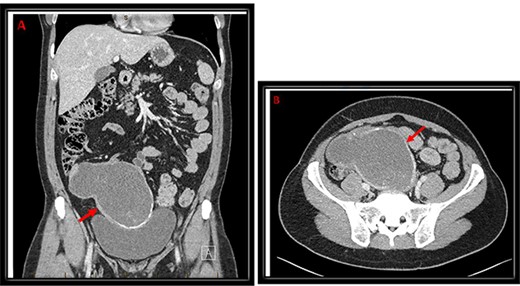

An abdominal ultrasound (US) was performed and showed a hypo-vascular mass in the right hypogastric region (Fig. 1). Abdomen and pelvis computed tomography (CT) scan with intravenous contrast identified a large complex mass (19.3 × 8.7 × 13.5 cm) with a partially calcified soft tissue rim with some internal calcifications. The mass extended from the central pelvis to the right lower quadrant of the abdomen (Fig. 2). The mass appeared to be attached to the cecum and no normal appendix was identifiable on imaging. There was no free fluid or evidence of metastasis. The tumor was compressing the bladder and sigmoid colon on CT scan, which explains the patient’s urinary and bowel symptoms.

Coronal (A) and transverse (B) cuts of CT abdomen/pelvis demonstrating a large complex mass (red arrow) extending from the central pelvis to the right lower quadrant of the abdomen with some calcifications at the inferior and medial edges with some internal calcifications.